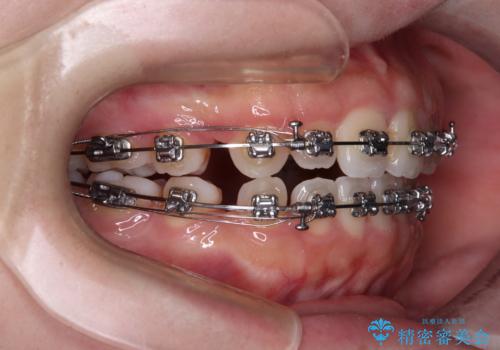

- メタルブラケット

- 1年9ヶ月

- 10-30回

当初は舌のトレーニングをしっかりと行ってくださったおかげで、短い期間で治療を終えることができました。